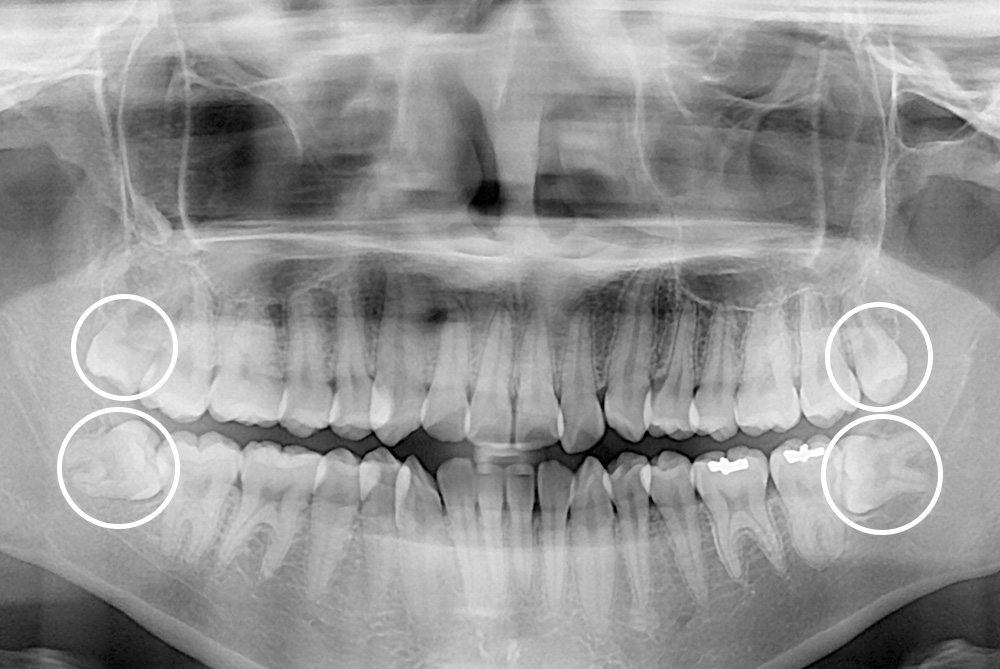

[사랑니] 매복 사랑니 발치

치료전 : 2019-08-12